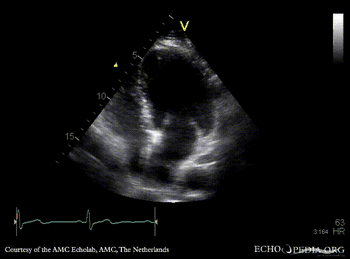

Cor triatriatum

A4CH: Cor triatriatum